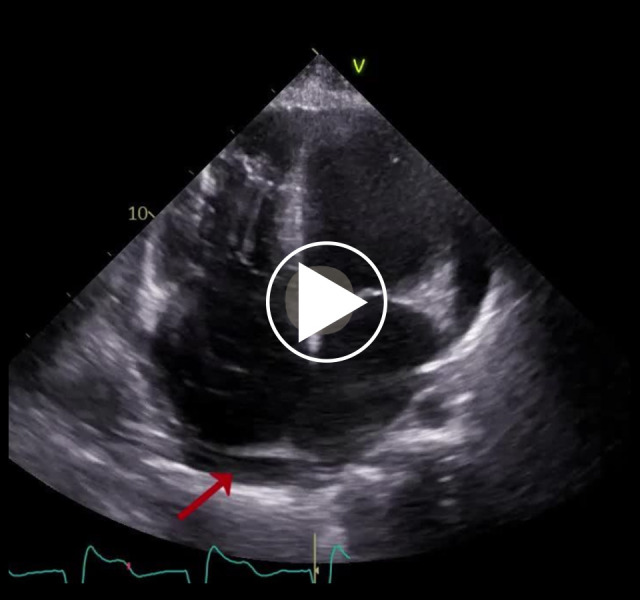

背景:卡恩斯-塞尔综合征(KSS)是一种罕见的遗传性线粒体疾病,以慢性进行性眼外麻痹、视网膜色素变性和心传导障碍为特征,发病年龄在20岁之前。该病还可表现为几种心血管(CV)疾病,如传导障碍或扩张型心肌病,并伴有神经肌肉和内分泌并发症。病例报告一名确诊为KSS的46岁男性在心脏移植(Htx)的鉴定过程中被心脏病研究所录取。患者的病史开始于诊断为三度房室传导阻滞,25岁时接受起搏器(PM)植入治疗。然而,由于左心室(LV)功能恶化的进展,PM在10年后升级为心脏再同步化除颤器治疗。入院前一年,患者因急性心力衰竭失代偿(ADHF)住院2次。入院时,体格检查显示充血特征。经胸超声心动图显示左室增大,整体运动功能减退,射血分数降低,右心室功能障碍。由于神经系统并发症和功能状况不佳,心脏小组同意对他进行保守治疗。由于ADHF的下一次住院治疗以患者死亡告终。结论:心血管疾病是治疗KSS患者的一个重要方面。我们的患者因并发症过度发展而转诊,因此他不能受益于Htx或机械循环支持。该病例强调了在并发症(包括心衰)完全发展之前对KSS患者进行早期诊断和监测的重要性。

BACKGROUND Kearns-Sayre syndrome (KSS) is a rare genetic, mitochondrial disorder characterized by a triad of chronic progressive external ophthalmoplegia, pigmentary retina degeneration, and cardiac conduction disorders, with onset before the age of 20 years. The disease can also manifest as several cardiovascular (CV) disorders, such as conduction disorders or dilated cardiomyopathy, along with neuromuscular and endocrinological complications. CASE REPORT A 46-year-old man diagnosed with KSS was admitted to the Institute of Heart Diseases in the qualification process for heart transplantation (Htx). The patient's medical history began with a diagnosis of third-degree atrioventricular block, treated with pacemaker (PM) implantation at age 25. However, due to progressing left ventricle (LV) function deterioration, PM was upgraded to cardiac resynchronization therapy with defibrillator 10 years later. In the year before the admission, he had undergone 2 hospitalizations caused by acute decompensations of heart failure (ADHF). Upon admission, physical examination revealed features of congestion. Transthoracic echocardiography showed an enlarged LV with global hypokinesia, reduced ejection fraction, and right ventricle dysfunction. Due to the neurological complications and poor functional condition, the Heart Team qualified him for conservative treatment. The next hospitalization due to ADHF ended in the patient's death. CONCLUSIONS CV disorders are an important aspect of treatment of KSS patients. Our patient was referred with excessively developed complications, so he could not benefit from Htx or mechanical circulatory support. This case highlights the importance of early diagnosis and monitoring of KSS patients before the full development of complications, including HF.